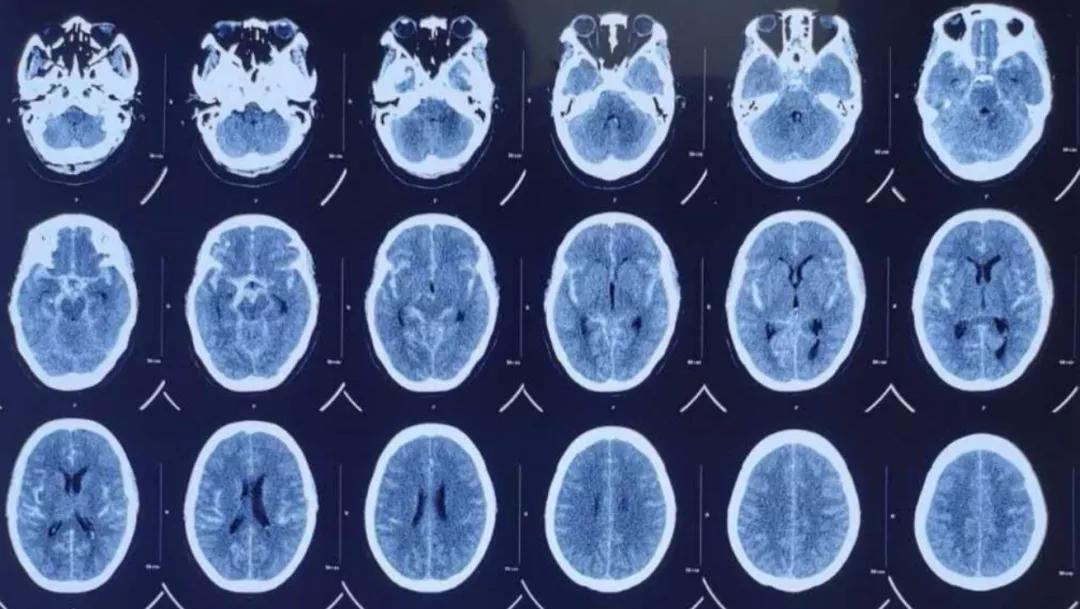

进入我科后,首先安排行头颅CTA检查,明确蛛网膜下腔出血是由于右侧颈内动脉末端动脉瘤破裂引起。动脉瘤生长在颈内动脉后交通段,位于后交通动脉对侧血管壁上,属于血泡样动脉瘤。(血泡样动脉瘤占所有动脉瘤的0.4%-2.7%,占破裂动脉瘤的6.6%,比较少见,但它非常容易再出血,死亡率极高,治疗也非常困难。)

术前影像学资料: